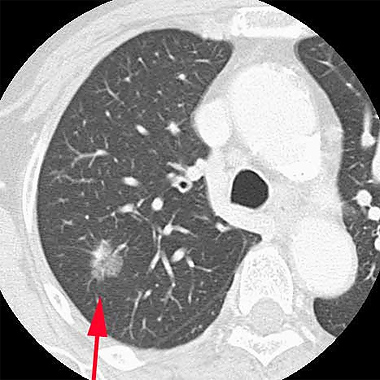

胸部レントゲンと胸部CTの違い

下の画像にあるように左が〈胸部レントゲン〉で右が〈胸部CT〉です。

左の〈胸部レントゲン〉の丸印のところが、右の〈胸部CT〉の矢印のところになります。このように、早期のがんは淡く小さな影で胸部レントゲンでは発見しにくいものです。

したがって、胸部の検診にはCTをお勧めしています。

胸部CT